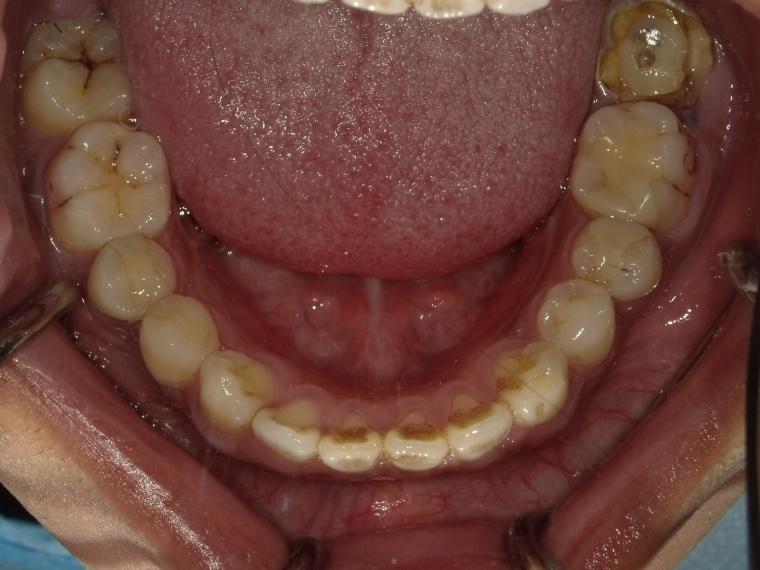

BEFORE

左下第二大臼歯が、残根の状態でご来院された患者さんです。

抜歯後に土台となる骨をつくる処置の後、インプラントを埋入しました。